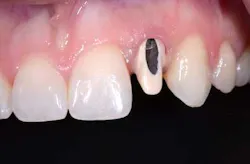

Fig. 1: There is a large access opening on the labial aspect of this UCLA abutment. The metal has been opaque and ceramic applied to allow the technician to use an all-ceramic restoration. Alternatively, a metal ceramic crown with a ceramic margin could be used.